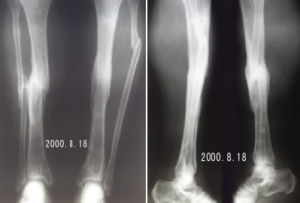

(一)彎曲型出生後脛骨下段向前彎曲,但無假關節,脛骨前弓處皮質增厚,髓腔閉塞,脛骨端萎縮硬化,呈前弓外形。發生骨折後,經一般處理局部不癒合,形成假關節。或因不認識此病,貿然作截骨手術,形成不癒合,繼續發展而兩斷端吸收,骨端硬化,遠端進一步萎縮變細,呈筆尖狀(圖1)。

先天性脛骨假關節圖1先天性脛骨假關節

本病主要是進行X線檢查:X線片可見脛骨中、下1/3前彎、成角、纖維囊性變和假關節形成,骨端變細呈錐形,骨端硬化髓腔閉鎖,骨皮質變薄,骨萎縮,脛骨遠端關節面可變形,腓骨可同時有假關節改變或彎曲畸形,小腿短縮。